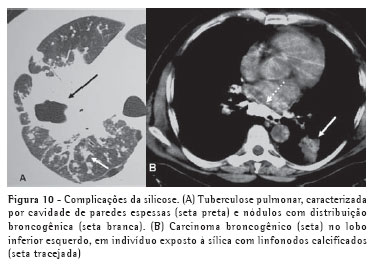

Os métodos de imagem também são muito úteis na avaliação de complicações da silicose, como a tuberculose pulmonar (silicotuberculose), infecções fúngicas e neoplasias pulmonares (Figura 10).